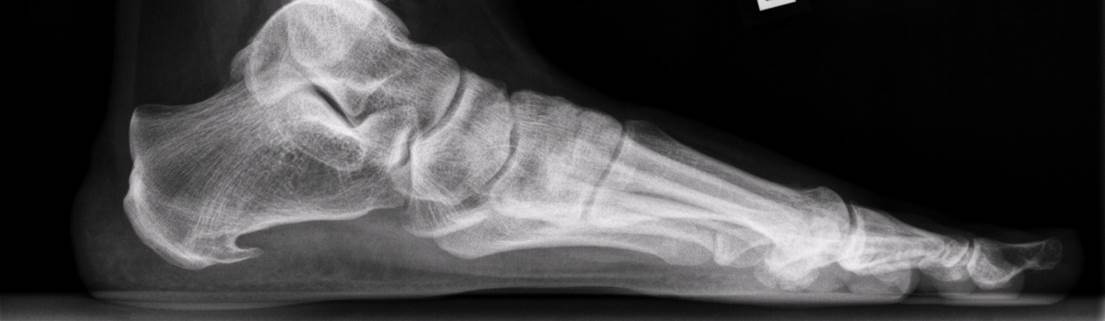

Een hielspoor is een verkalking aan de onderkant van het hielbot (calcaneus). Deze zit bij de aanhechting van de peesplaat die naar de voorvoet loopt. Een hielspoor is waarneembaar op röntgenfoto, maar ook is hij goed te zien op een echo.

Hielspoor op röntgenfoto